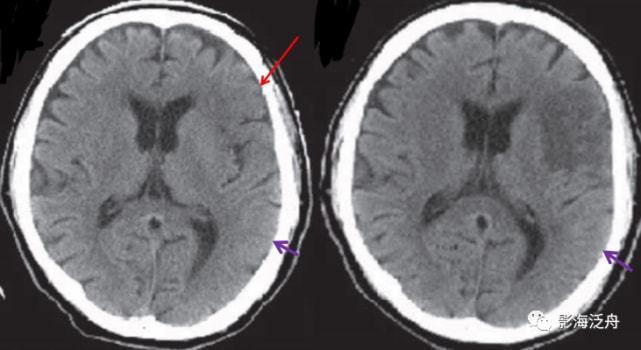

汇总| 超早期脑梗死ct征象

脑梗死丨演变,血供区域分布,ct表现

夜班不求人急性脑梗死的ct诊断

手把手教程:脑梗死影像读片入门

脑梗塞ct诊断

脑梗死CT

脑梗死ct影像表现图片

ct脑梗死图片讲解

腔隙性脑梗塞ct图片

基底节区脑梗塞ct图片

脑梗死ct影像图片

脑梗死ct图片

脑梗塞ct图片解说图